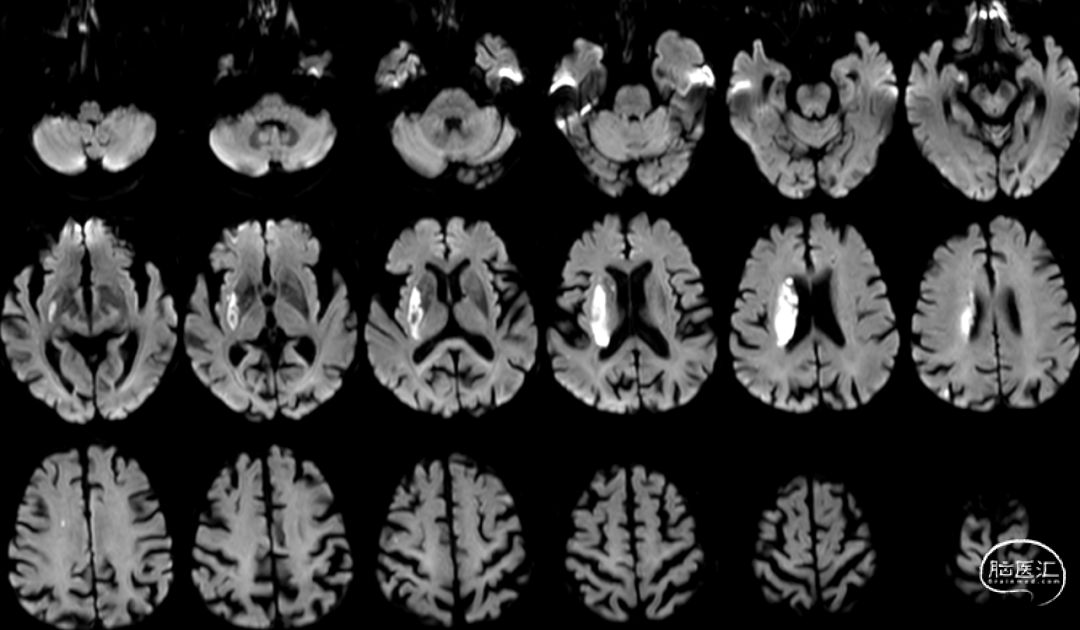

Cranial DWI:右侧壳核、侧脑室旁小片状+皮层点状弥散受限。

Cranial SWI:SVS+AHVs RMCA M1长条血栓。

T2 Flair:丰富的高信号血管征(HVS)。

Reexamination Cranial DWI:无明显的血栓向远端逃逸或小血栓脱落后新形成的皮层或分水岭点片状梗死。

Reexamination Cranial T2 Flair。